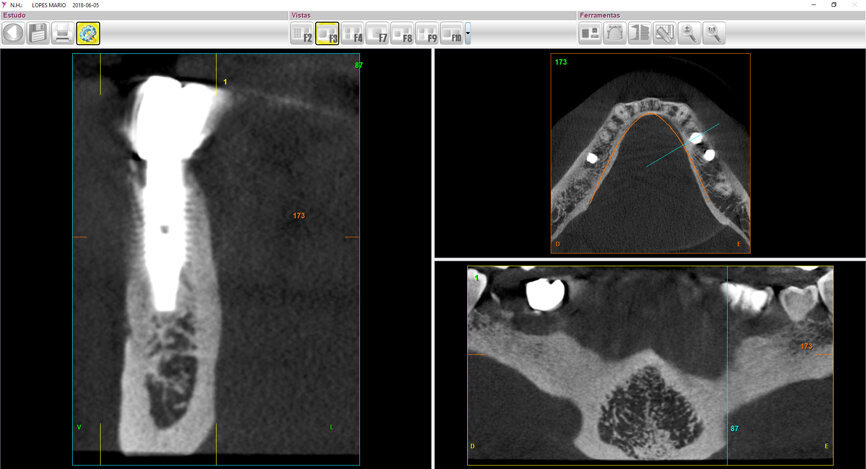

Fig. 1c: Initial situation: apical radiograph (a), intra-oral view (b) and CT scan (c).

After analysing the computed tomography (CT) scan on BTI Scan II software (BTI Biotechnology Institute; Fig. 1c), the root was not considered to have the minimum criteria for retaining a crown, or a post and core and crown. As the bone availability, bone density and remaining buccal bone were considered to be ideal, implant therapy was immediately considered.

This CT scan was taken three years before the root fractured. As there was no infection related to the root and sulcus probing, all around the remaining root and all the way down to bone contact showed no socket alteration—a Type I socket was diagnosed—it was decided not to irradiate the patient further. This CT scan data, supported by the clinical examination, was considered reliable, despite the three years that had passed.

The two-year follow-up postoperative cone beam computed tomography (CBCT) scan (Figs. 11 & 12), as well as the clinical photographs, illustrated the bone level, the buccal bone volume achieved and maintained over the period. Also, it was possible to see that the gap distance, radiographically, appeared to have been filled with bone. It was surprising also to see that bone level was well above the implant–abutment junction, maybe in response to a very efficient maintenance of a zero micro-gap at the junction owing to this BioBlock (BTI Biotechnology Institute) one abutment, one time concept, providing a virtual one-piece implant.